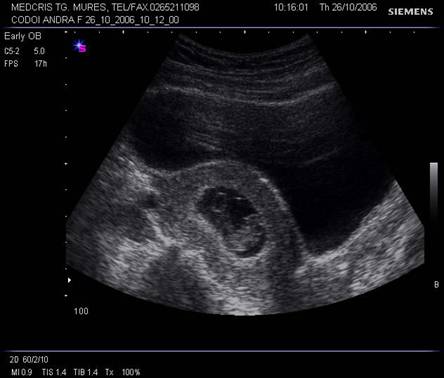

Fig. nr.125 Omfalocel la o sarcina de 12 saptamani ( zona anecogena marcata cu caliper )

Fig. nr.126 Acelasi fat ca in figura precedenta, sectiune transversala abdominala, cu ecou Doppler la periferia omfalocelului

Fig. nr.127 Avorton de 12 saptamani gestationale corespunzator ecografiilor anterioare, cu omfalocel, sacul herniar rupt postabortum